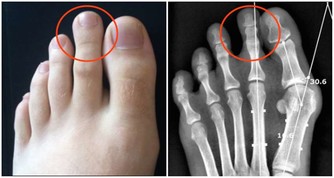

取穴位置

腳背大拇趾和第二個腳趾,夾縫向上的凹陷處。